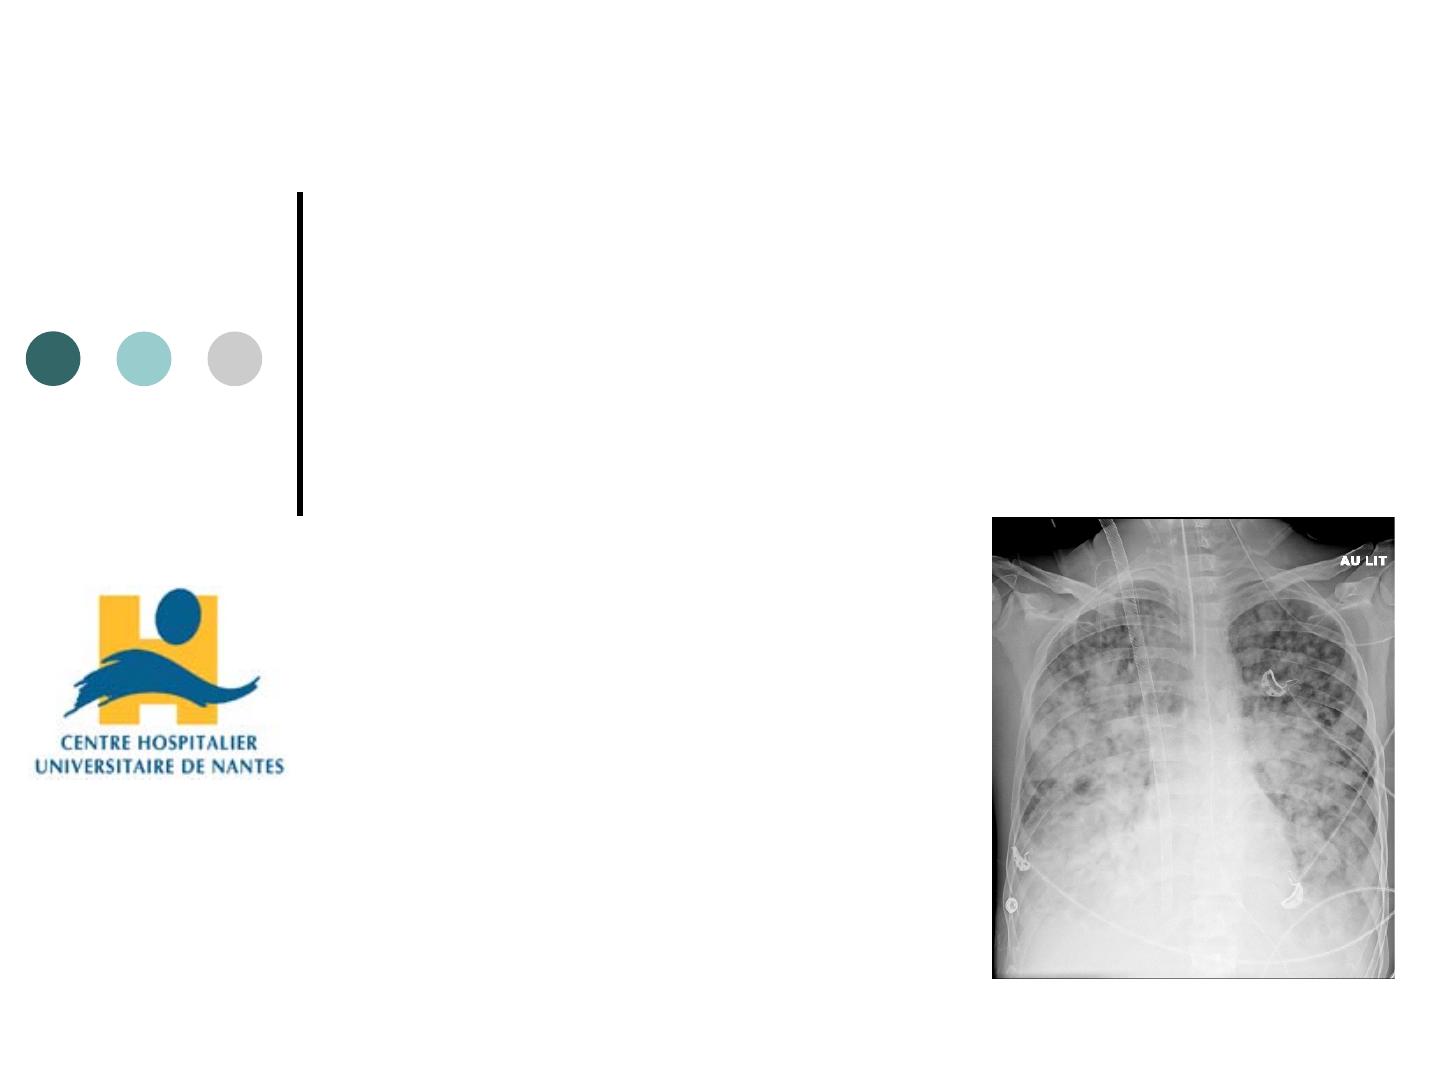

Mucoviscidose ECMO VV

canule jugulaire double lumière